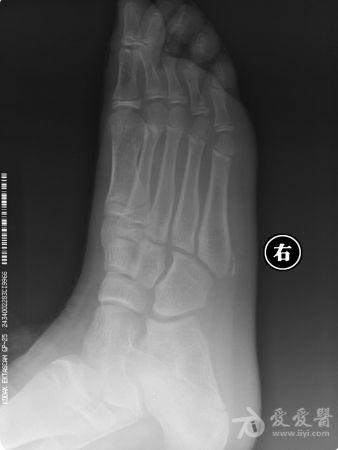

- X线片:是首选的检查方法,可以清晰显示骨骼形态,判断是否存在骨折、骨折类型、骨骺损伤、骨软骨瘤等。

(图4示意:儿童第五跖骨基底骨折的X线片示意图,标注骨折线;图5示意:骨软骨瘤的X线/CT示意图,显示菜花状骨性突起)